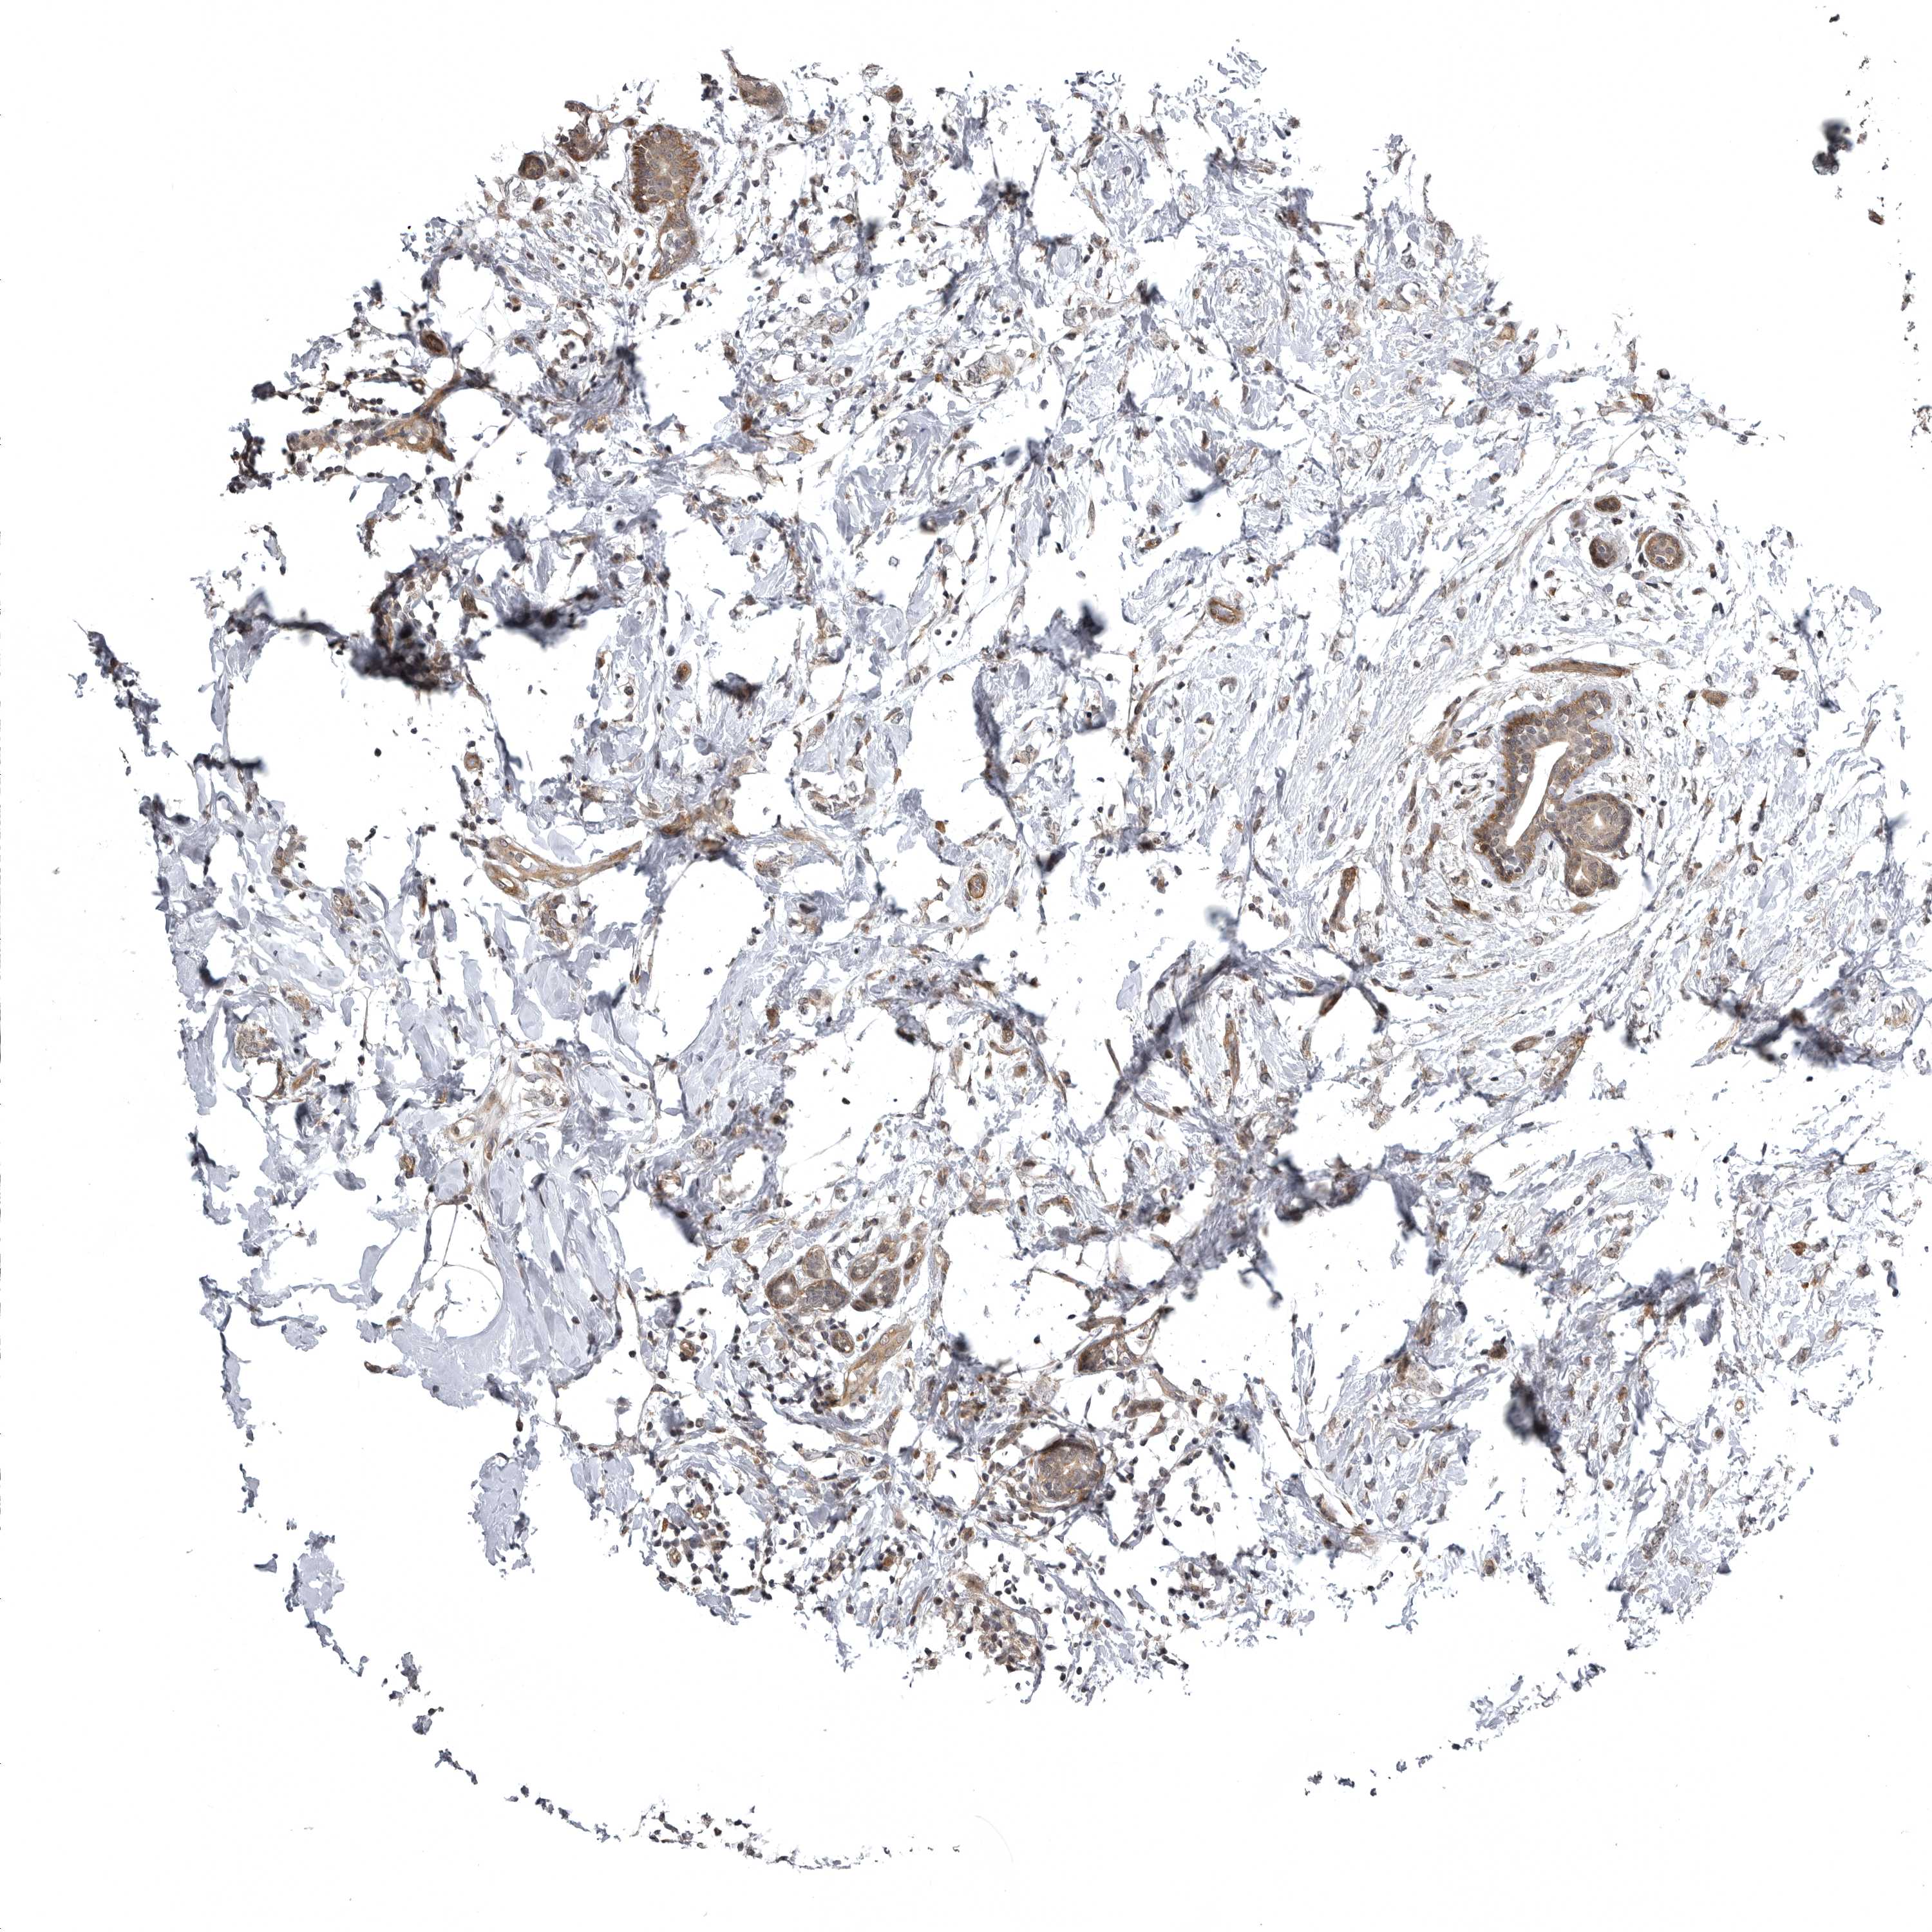

CANCER BREAST CANCER Show tissue menu

BRCA TCGA BRCA VALIDATION PROTEIN EXPRESSION

ANTIBODIES

AND

VALIDATION